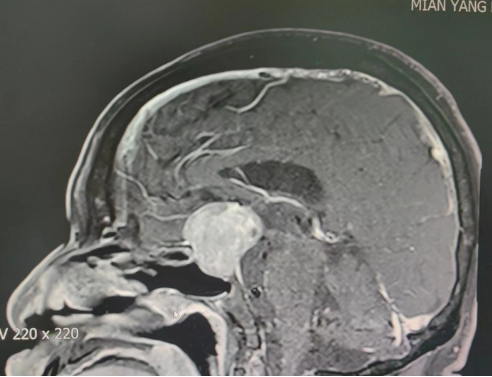

术前影像学检查

为挽救郭大爷的生命和视力,绵阳三医院神经外科决定为其进行经鼻手术切除。但由于郭大爷长期吸烟饮酒,还患有糖尿病及高血压,进一步增加了手术和麻醉风险。经我院副院长、神经外科专家刘阳与医疗团队讨论,决定在神经内镜的配合下切除肿瘤,这样既避免了对肿瘤周围结构的损伤,也能减少术中出血,加快肿瘤的切除速度。